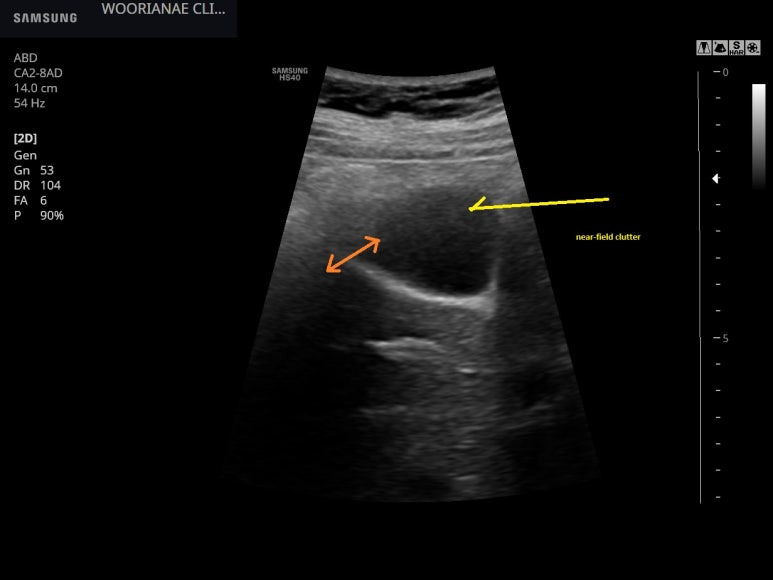

초음파 시행, 담낭저부가 장과 닿으면 경계가 모호할수가 있으며..

작은 용종

다른 각도에서 저부의 끝까지 포함하여 관찰하기위한 노력

Near field effect로 앞쪽 담낭벽이 명료하지 않으나

담낭 밖으로 연결되는 (주황화살표) 음영이므로 artifact, 허상

담낭용종이외에 특이소견 없어 1년뒤 추적하기로 하였다.

Near-Field Clutter Structures in the near field are sometimes obscured because of the high amplitude of oscillations by the transducer itself, causing socalled near-field clutter.7 This is especially relevant in case an apical ventricular thrombus is suspected.